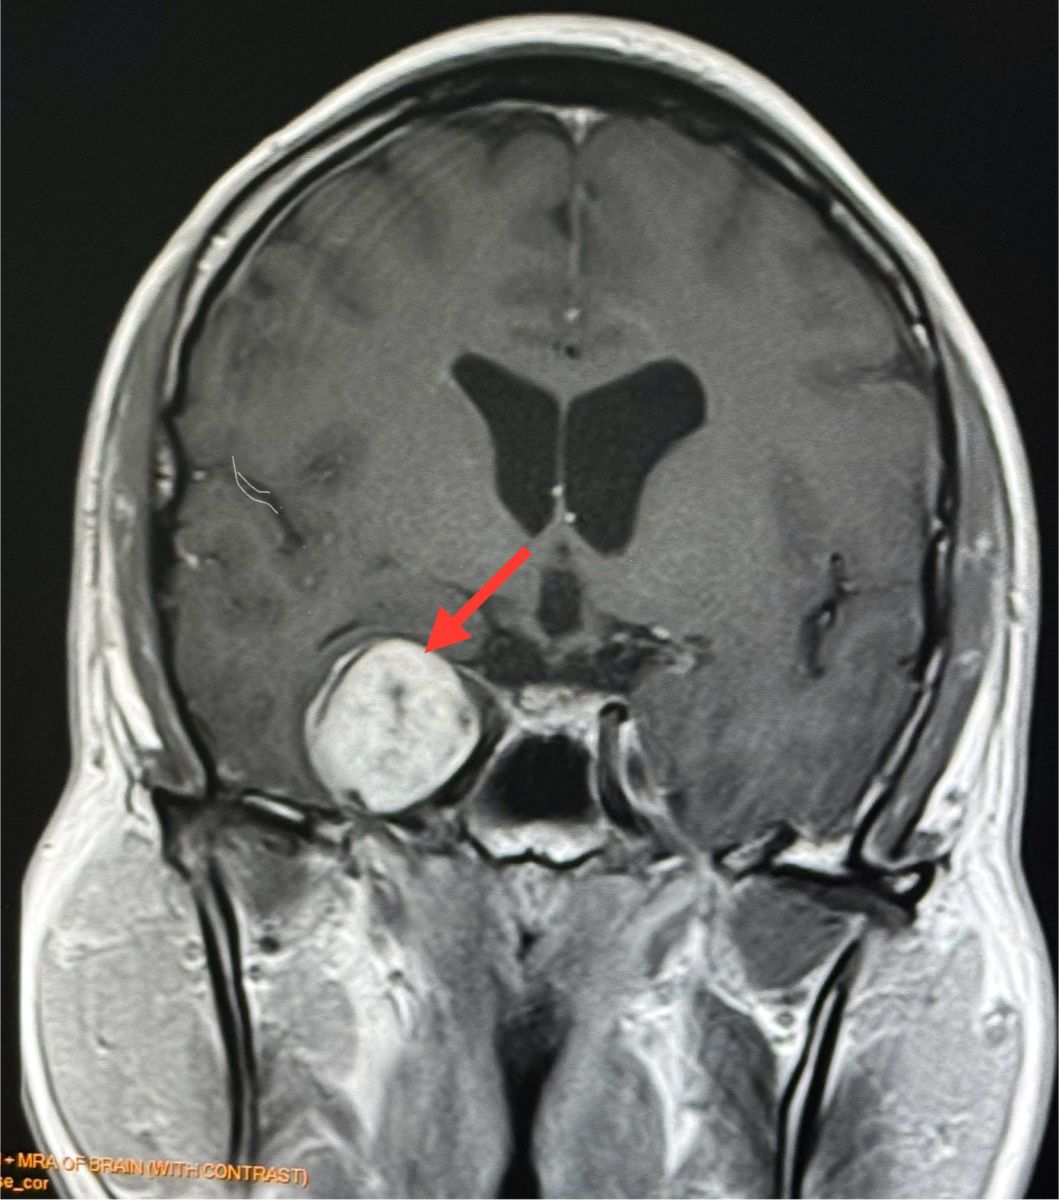

ทำคอมพิวเตอร์ CT สมองพบก้อนขนาด 2.7 × 3.0 × 2.9 เซนติเมตร ที่กลีบขมับของสมองด้านขวา right temporal lobe ทำ MRI (Magnetic Resonance Imaging) โดยใช้คลื่นแม่เหล็กไฟฟ้าและคลื่นวิทยุความถี่สูงและฉีดสี พบก้อนขนาด 3.1 × 2.9 × 2.9 เซนติเมตร สงสัย Trigeminal Schwannoma เนื้องอกของปลอกประสาทเส้นประสาทสมองเส้นที่ 5 ข้างขวา

อาการปวดศีรษะหายเอง ไม่ปวดอีกเลย ผู้ป่วยมีเนื้องอกในสมอง ตรวจเจอโดยบังเอิญจากการทำคอมพิวเตอร์สมอง

Trigeminal Schwannoma คือเนื้องอกชวานโนมาที่เกิดจากเซลล์ชวานน์ (Schwann cells) ซึ่งเป็นเซลล์ที่ทำหน้าที่สร้างเยื่อไมอีลินที่ห่อหุ้มเส้นประสาท โดยเนื้องอกชนิดนี้เกิดขึ้นบริเวณเส้นประสาทไทรเจมินอล ซึ่งเป็นเส้นประสาทสมองเส้นที่ 5 เนื้องอกชนิดนี้พบน้อยมากๆ ส่วนใหญ่เป็นเนื้องอกไม่ร้ายแรง (benign) โตช้า รักษาด้วยการผ่าตัด หรือฉายแสง